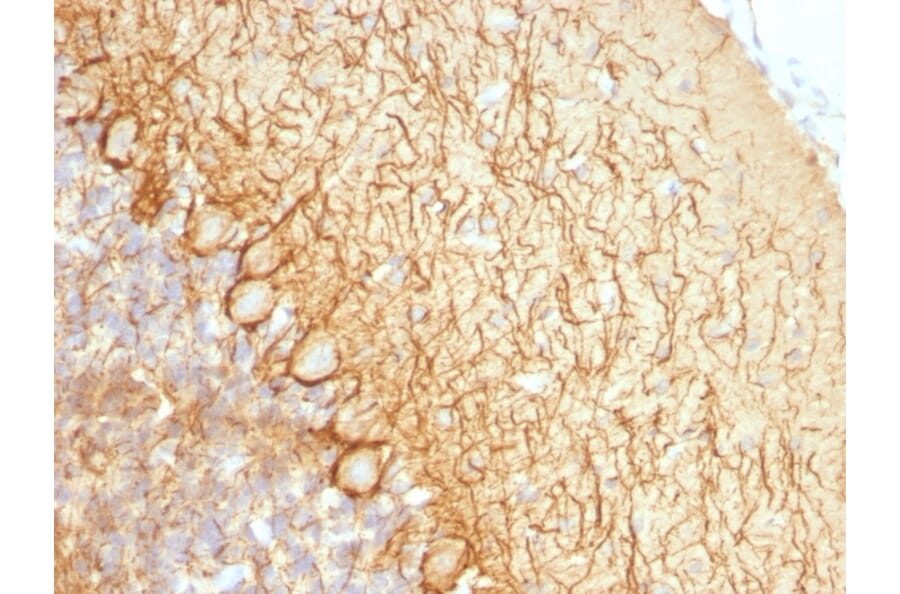

This antibody reacts with a 68kDa protein, identified as light sub-unit of neurofilaments (NF-L). Neurofilaments make up the main structural elements of axons and dendrites and are found in neurons, peripheral nerves, and sympathetic ganglion cells. Neurofilaments consist of three major subunits with molecular weights of 68kDa (NF-L), 160kDa (NF-M) and 200kDa (NF-H). Anti-neurofilament stains a number of neural, neuroendocrine, and endocrine tumors. Neuromas, ganglioneuromas, gangliogliomas, ganglioneuroblastomas, and neuroblastomas stain positively for anti-neurofilament. Neurofilaments are also present in paragangliomas as well as adrenal and extra-adrenal pheochromocytomas. Carcinoids, neuroendocrine carcinomas of the skin, and oat cell carcinomas of the lung also express neurofilament.

IF, Flow Cytometry, IHC-P

IF: 1-2 µg/ml, Flow Cytometry: 1-2 µg/million cells, IHC-P: 1-2 µg/ml